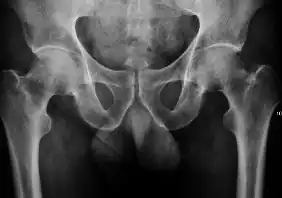

Projectional radiography ("X-ray") is the first imaging technique of choice in hip pain, not only in older people with suspected osteoarthritis but also in young people without any such suspicion. In this case plain radiography allows categorization as normal hip or dysplastic hip, or with impingement signs, pincer, cam, or a combination of both.[1]

X-Ray

Projectional radiography ("X-ray") is currently useful not only in older people in whom osteoarthritis of the hip is suspected but also in younger people without osteoarthritis, who are being evaluated for femoroacetabular impingement (FAI) or hip dysplasia.[1]

Plain radiography allows us to categorize the hip as normal or dysplastic or with impingement signs (pincer, cam, or a combination of both). Besides these, pathologic processes like osteoarthritis, inflammatory diseases, infection, or tumors can also be identified (Figure 1).[1]

Figure 1.

-

Radiography in normal hip -

X-ray in pincer impingement type of hip dysplasia -

X-ray of cam -

Hip in osteoarthritis -

Septic arthritis

X-ray in pediatrics